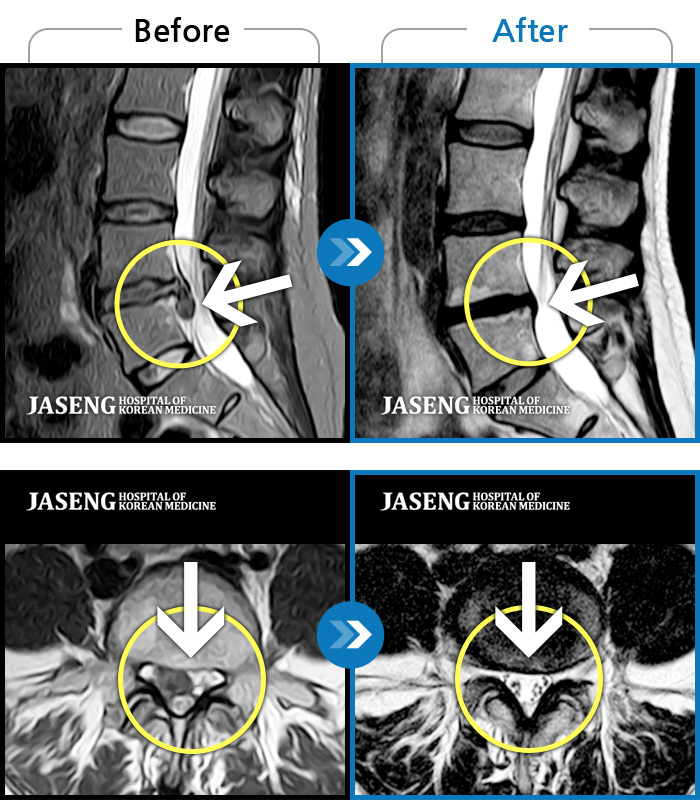

MRI ũ ʸ Ȯϼ.

ȯںп Ǹ ǿ ԿǾ, ο ġ ۿ Ƿ ġḦ Ͻñ ٶϴ.